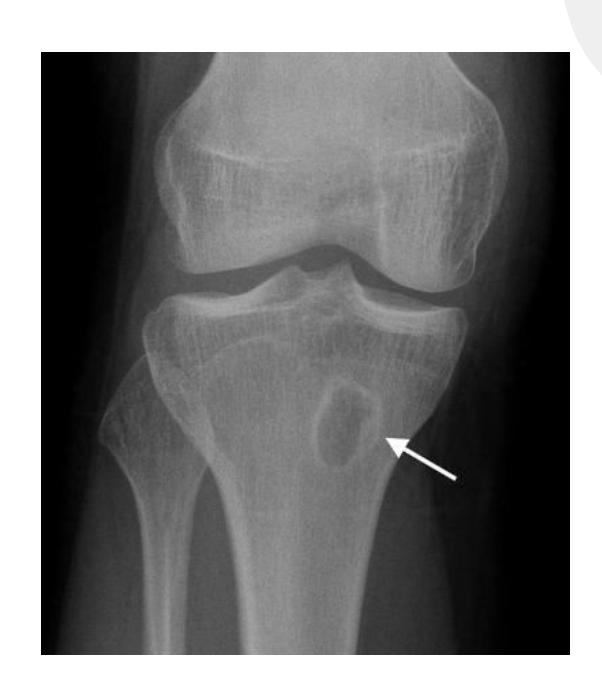

A teenager with acute onset of pain in the right hip during a run. He sustained the injury seen in the x-rays with a white arrow. This injury usually occurs due to a forceful eccentric contraction of which of the following muscles?

- C. Rectus femoris

- Sartorius

Which of the following muscles is attached to the structure pointed by the arrow?

- C. Sartorius

Note: Arrow was pointing at ASIS (Anterior Superior Iliac Spine)